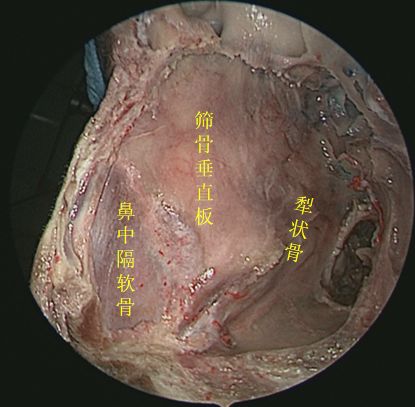

切除中鼻甲后观察鼻腔内整体空间形态

侧方观察右侧鼻腔侧壁结构

45度角观察右侧鼻腔侧壁

切除右侧中鼻甲后观察右鼻腔侧壁

切除中、下鼻甲后抵近观察右侧鼻腔侧壁